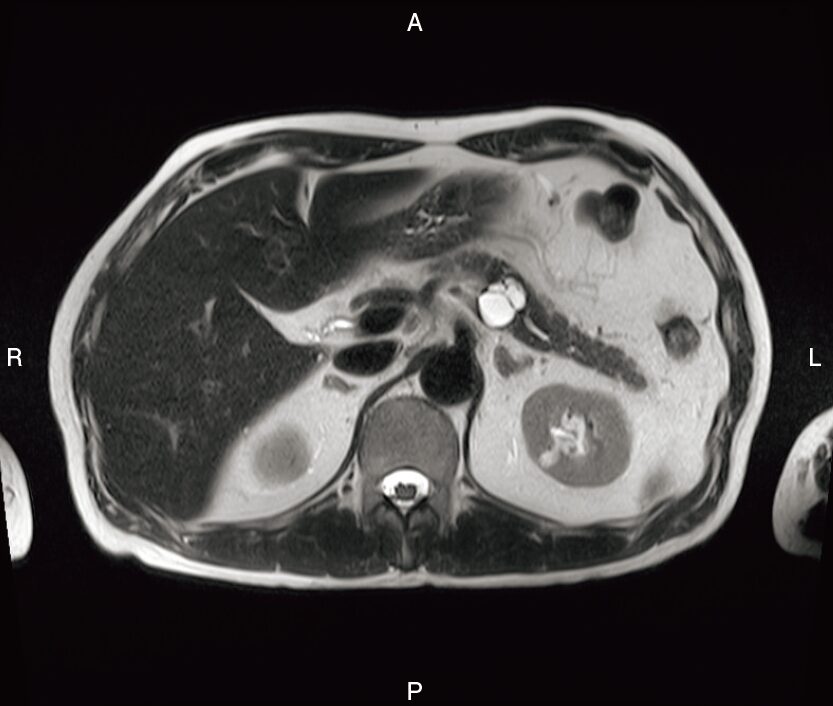

腹部 MRI の T2 強調像を示す。 多房性の腫瘤が存在する臓器はどれか。

3.膵 臓

- 今回の膵臓の病変は、まさにこのタイプです(IPMN:膵管内乳頭粘液性腫瘍の分枝型などが疑われます)。

まず、T2強調像で真っ白に光っているという「信号特性(=水・液体)」。 次に、内部に隔壁を持ち、ブドウの房のようになっているという「形態(=多房性)」。 そして、「解剖学的位置関係(=膵体部)」。

これら3つの要素を総合的に判断して、「IPMN疑い」と導き出せる。それができればボーナスで3点、、、といきたいとこじゃが、この問題は「解剖学的位置関係」さえわかっておればまず落とさんじゃろ。

- この画像の正体である可能性が高い「膵IPMN(膵管内乳頭粘液性腫瘍)」は、検診や腹痛など、全く別の目的で撮ったCT・MRIで「たまたま見つかる(偶発発見)」ことが非常に多いです。 我々技師がCTやMRIを撮っていると、けっこう遭遇するポピュラーな病変の一つです。